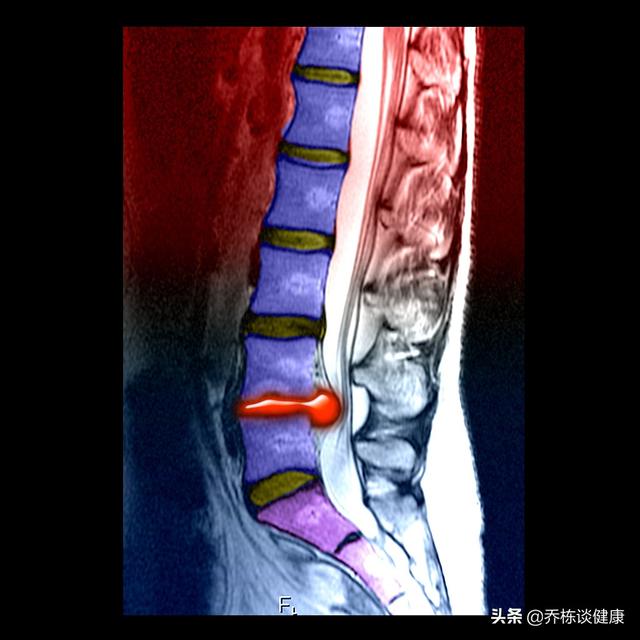

La sténose rachidienne lombaire, qui décrit en fait un diamètre réduit du canal rachidien, peut être déclenchée par un certain nombre de facteurs, par exemple un canal rachidien plus étroit à la naissance, ou en raison d'ostéophytes, ou de tumeurs, et bien sûr le plus courant est la hernie discale lombaire qui prend le dessus et conduit à la sténose rachidienne, et au cœur de tout cela, ce sont les symptômes qui comptent.

La sténose rachidienne lombaire est le phénomène, la maladie de la sténose rachidienne lombaire est la maladie. Quels sont les symptômes de la sténose spinale lombaire ? Les principales manifestations sont des douleurs lombaires, des courbatures ou des faiblesses, un engourdissement ou une faiblesse des jambes. Le symptôme le plus typique est la claudication intermittente, c'est-à-dire que plus vous marchez, plus vos jambes sont douloureuses et faibles, et vous devez les soulager en vous accroupissant ou en vous penchant, puis en continuant à marcher, alors que cette situation n'est pas gênante lorsque vous faites du vélo, et vous pouvez faire ce que vous voulez. Notez que la sténose spinale lombaire ne provoque pas de douleurs dans les jambes, et que les douleurs dans les jambes sont généralement observées dans le cas d'une hernie discale lombaire. La différence entre les deux est simple, il suffit de faire un test d'élévation de la jambe droite, la sténose rachidienne lombaire peut être faite, la hernie discale lombaire ne l'est catégoriquement pas.